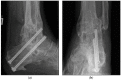

Joint destruction necessitates tibiotalocalcaneal arthrodesis (TTCA) in cases of clinical deficits that cannot be controlled conservatively, possibly leading to sepsis. We aimed to compare the underlying etiology of posttraumatic joint destruction and the outcomes after TTCA in patients with a septic or aseptic history. Between 2010 and 2022, 216 patients with TTCA were retrospectively enrolled (septic TTCA (S-TTCA) = 129; aseptic TTCA (A-TTCA) = 87). Patient demographics, etiology, Olerud and Molander Ankle Scores (OMASs), Foot Function Index (FFI-D) scores, and Short Form-12 Questionnaire (SF-12) scores were recorded. The mean follow-up period was 6.5 years. Tibial plafond and ankle fractures were the most common causes of sepsis. The mean OMAS was 43.0; the mean FFI-D was 76.7; and the mean SF-12 physical component summary score was 35.5. All the scores differed significantly between the groups (p < 0.001). With an average of 11 operations until the arthrodesis was achieved, the S-TTCA patients underwent about three times as many operations as the A-TTCA patients (p < 0.001), and 41% of S-TTCA patients remained permanently unable to work (p < 0.001). The significantly worse results of S-TTCA compared to A-TTCA show the long and stressful ordeal that patients with a septic history suffer. Further attention must be paid to infection prophylaxis and, if necessary, early infection revision.